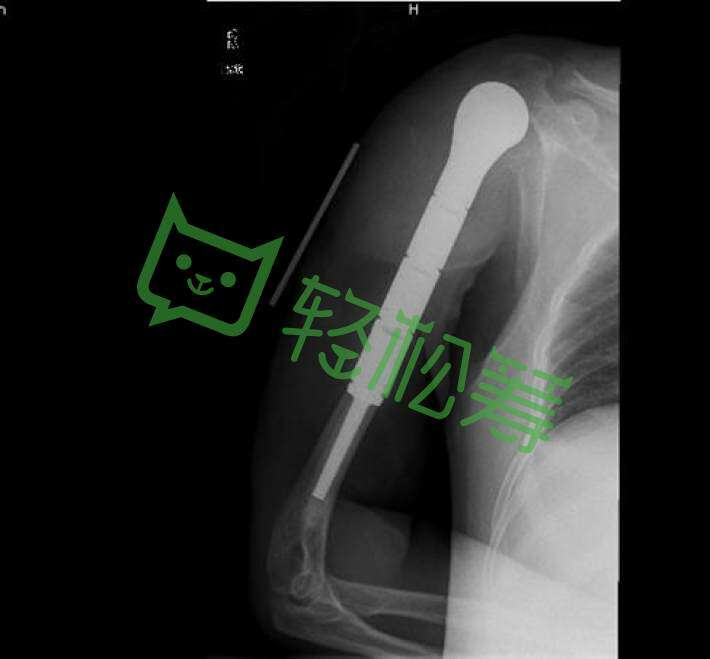

我叫唐国超,现年32岁,祖籍自贡富顺县,现居住地为:四川省平昌县新平街.与患者唐纯炎系父子关系。我的父亲唐纯炎现年54岁,父亲从2017年7月份开始感觉到自己手臂酸痛难受、以为是肩周炎颈椎病、只做了常规的按摩理疗,直到2017年10月份的一天、手臂突然自动断裂,当即送往平昌县中医院检查无果、随即转往达州市中心医院治疗、条件有限均无法治疗!最后转往成都华西医院检查确诊为恶性肿瘤软骨肉瘤(系癌症2级)前后2017年11月做了肩关节置换手术与肿瘤切除手术,如今刚过3个月,癌细胞扩散至肩臂,马上又要面临高位截肢手术!手术让我们这个本来就不富裕的家庭雪上加霜!母亲又常年生病一直在家,均无业无保险。经医院告知:今后还将面临大额资金的开支才可以留住父亲的生命,让我父亲能够多活几年,当儿子的如今已一贫如洗!无法承担高昂的医疗费,经好心人士提醒申请轻松筹,望社会各界好心人能献出一份爱心、让一辈子都在操劳的父亲战胜病魔坚强的活下去!谢谢好心人!